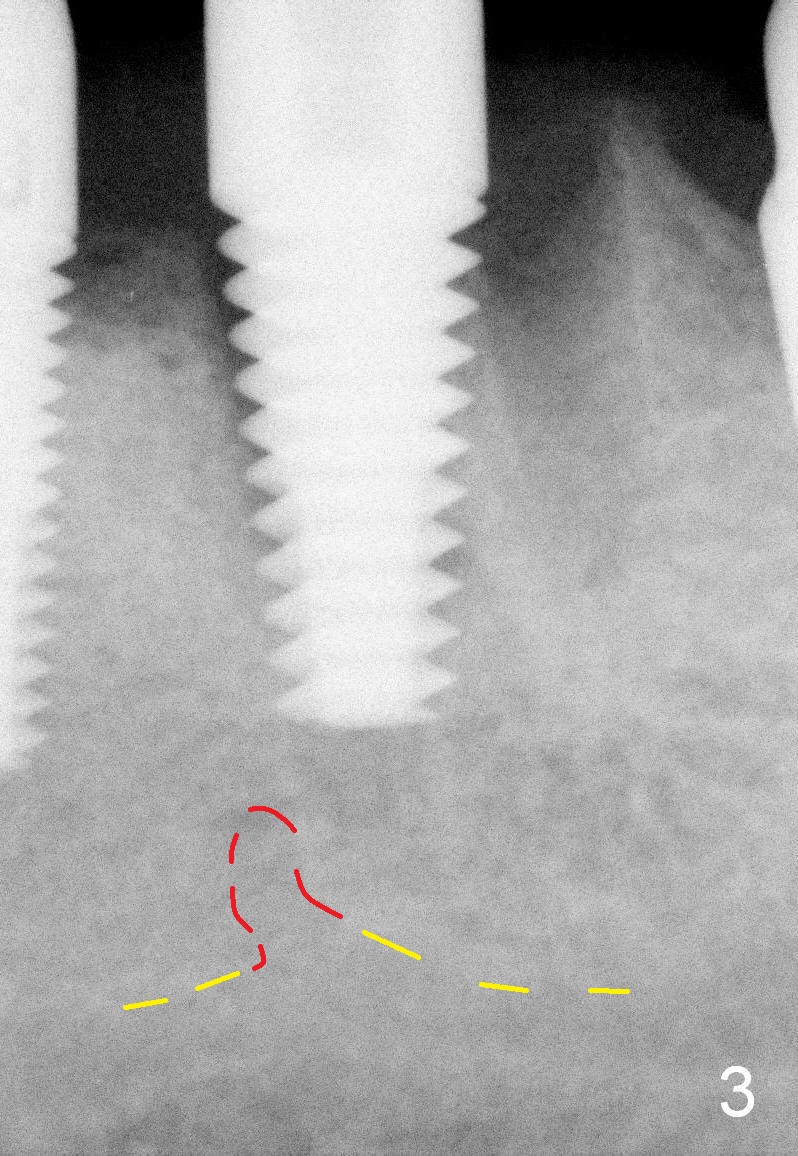

When the infection at the site of #20 is under control, the tooth #19 causes severe pain with mesial periapical radiolucency (Fig.1 *). Vertical mesial root fracture is confirmed at extraction. Osteotomy is initiated in the septum (Fig.2 S), but the apical end of the 2 mm pilot drill deviates to the mesial socket. A Lindamann bur is used to move osteotomy distal, but the implant (6x17 mm) is mainly placed in the mesial socket (Fig.3). An intraop drawback associated with the deviation is pain control. The nervous patient questions several times whether it is a good idea to place an implant in the infected site. Block anesthesia has to be administered. In fact lack of pain control may be also related to proximity to the Mental Loop (Fig.3 red dashed line). Fortunately no paresthesia occurs postop, since the implant is somehow placed lingually.